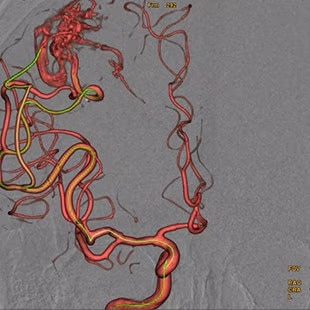

Vessel assist for neurointerventional

Vessel ASSIST delivers accurate and easy anatomy segmentation and accurate vessel quantification from 3D volumes. It also offers advanced 3D roadmap and augmented image guidance capabilities on frontal or lateral planes to guide catheter with confidence for procedure such as Aneurysm Treatment with Flow Diverter.

Plan

Segment and size the anatomy of interest in CBCT.1 Plan the stent positioning on the 3D model and prepare 3D landmarks to help guide the deployment.

Guide

Import segmented anatomy, centerline and landmarks and overlay them on live fluoroscopy on the frontal or lateral plane for 3D fusion guidance.